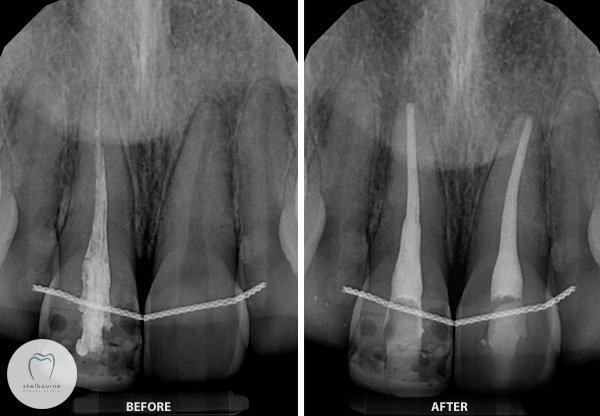

So, what did I do here? Simple really – I had to remove the less-than-ideal root canal filling from the ‘blue dot’ tooth, clean the canal properly and replace it with a more satisfactory one. (And also root canal treat the other tooth beside it!) Thankfully we were able to get Mary out of pain!

See my final digital x-ray below.

Left Image: Before Treatment. Right Image: After Treatment